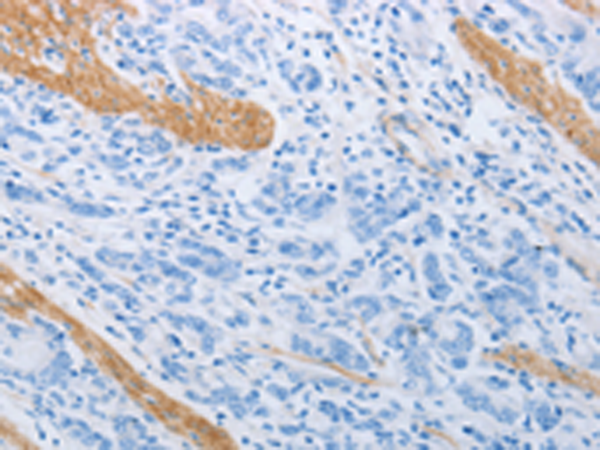

分类: 科研抗体货号: P10652别名:应用: WB,IHC反应种属: Human, Mouse